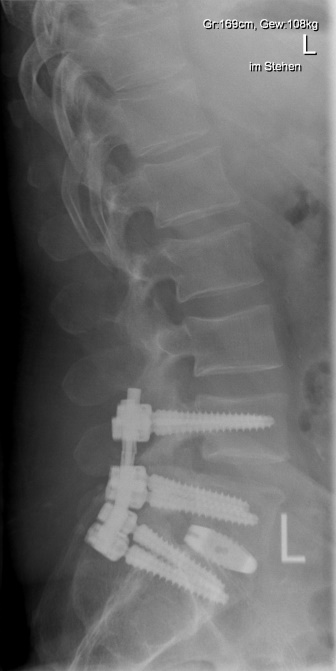

Beispiel Osteochondrose

Der Begriff Osteochondrose beinhaltet den Verschleiß eines oder mehrerer Bewegungssegmente der Wirbelsäule. Häufigste Lokalisation ist der Zwischenwirbelraum der unteren Lendenwirbelsäule. Dabei kann es durch den Verschleiß der Bandscheibe zur lokalen Rücken/Nacken-Beschwerden kommen oder durch daraus resultierende Instabilität eine Spinal- oder Nerveneinengung mit ausstrahlenden Beschwerden verursachen. Im fortgeschrittenen Stadium kann dies auch zu ausgeprägten Wirbelsäulenverkrümmungen führen, die dann möglicherweise einen "Ganzwirbelsäulenschmerz" verursachen. Die Therapie der Wahl bei Osteochondrose an der Lendenwirbelsäule ist nach Ausschöpfung der konservativen Therapiemaßnahmen die Spondylodese oder Versteifung. Dabei werden nur die betroffenen Bereiche mit einem Schraubenstabsystem überbrückt und die verschlissenen Bandscheiben durch einen Platzhalter ersetzt.